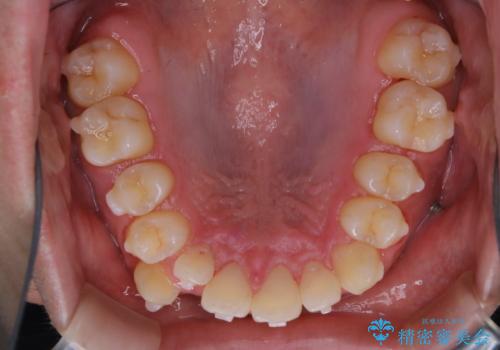

- マウスピース矯正中に、口臭が気になりクリーニングを行いたいとのことでした。染め出しをしての歯ブラシ指導とPMTC60分コースを行いました。

口腔内にはたくさんの細菌がいるため、ヌルヌルとしたプラーク(歯垢)が自然に歯の表面に付きます。

このプラーク(歯垢)にはたくさんの細菌が潜んでおり、虫歯や歯周病・口臭などの最大の原因です。そのため、毎日の歯磨きでプラーク(歯垢)をキレイに取り除くことが、健康な歯を保つためには欠かせません。

しかし、プラークは歯の色と似ているため、見ただけでは付着しているかどうかがハッキリとは分かりません。

染め出し液を使ってプラークを染め出すことにより、普段の歯みがきで磨き残している場所を目で確かめることができます。

日々の歯磨きを上達するには、まずどこが磨けていないか認識することが大切です。